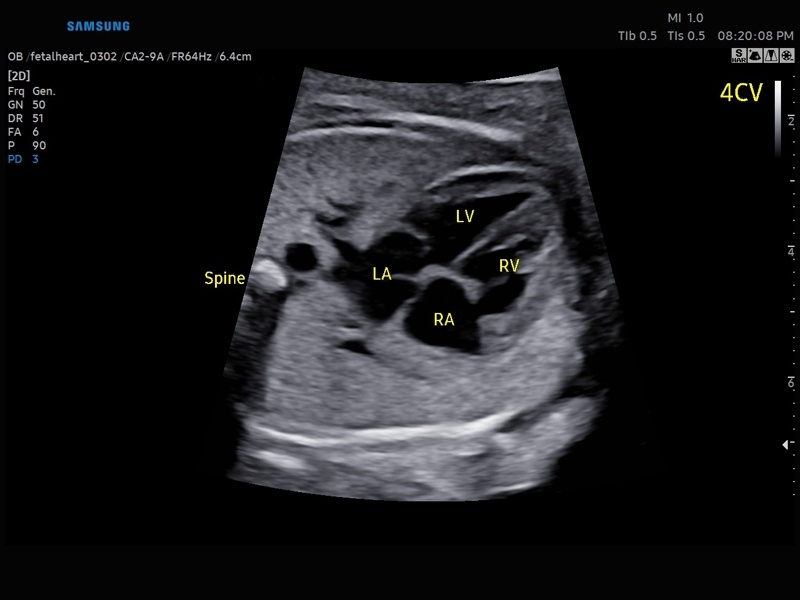

• Сердце плода:измерения в В-режиме (отношение площади сердца и грудной клетки), измерения в М-режиме (толщина межжелудочковой перегородки в диастолу, конечнодиастолический размер левого желудочка, толщина задней стенки левого желудочка в диастолу, толщина межжелудочковой перегородки в систолу, размер левого желудочка в систолу, толщина задней стенки левого желудочка в систолу, внутренний размер правого желудочка в диастолу), измерения в режиме спектрального допплера (легочный ствол, артериальный проток, нижняя полая вена, венозный проток, восходящая аорта, нисходящая аорта, трансмитральный кровоток, митральная регургитация, трикуспидальный кровоток, трикуспидальная регургитация, индекс преднагрузки, ЧСС).

• МодульSTIC- объемная динамическая визуализация сердца плода.

• Модуль5D HeartColor – программа автоматического построения основных срезов средца плода в режиме объемного сканирования с анализом кровотока.